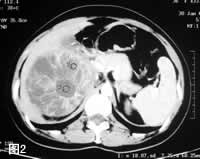

MRI:病灶T2WI呈高信号强度,多房状结构清楚,间隔为低信号,右肾静脉及下腔静脉内未见瘤栓征象(图3)。冠状层面显示肿瘤与残余肾下极间分界清楚,外缘光滑(图4)。